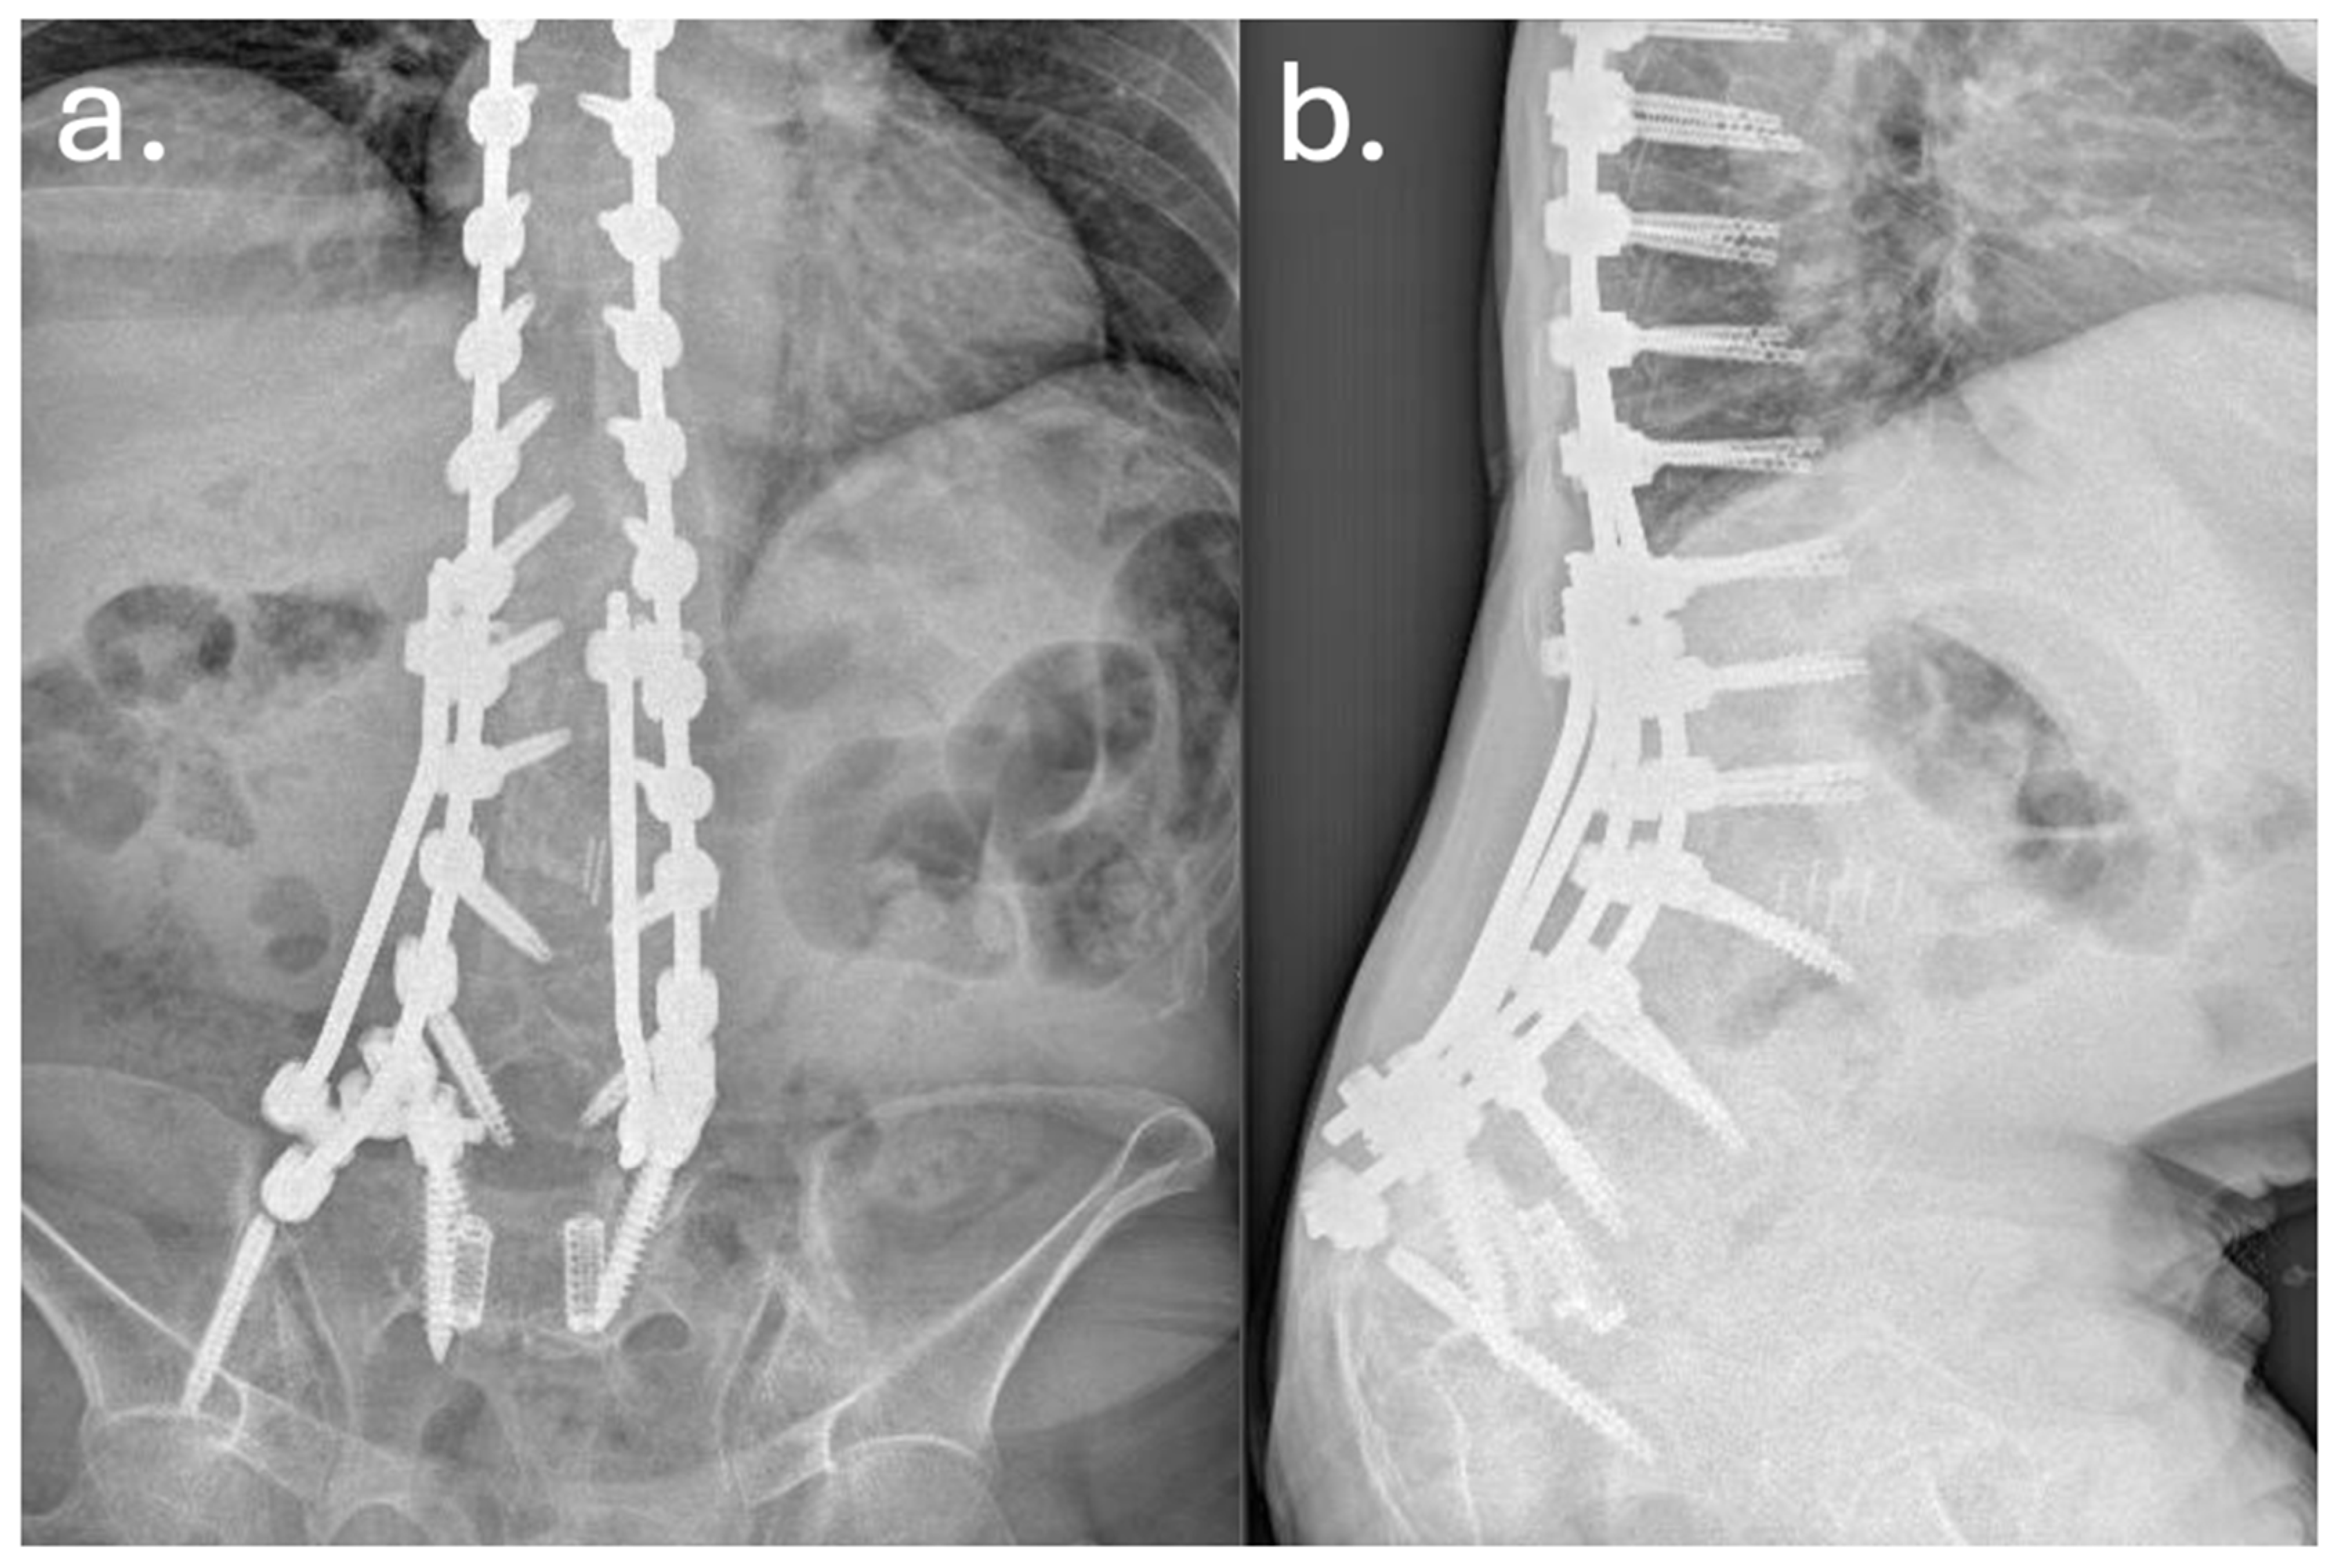

3. Case Report

| Year | Event |

|---|---|

| Dec 2010 | Posterior decompression and L5–S1 fusion |

| Apr 2012 | Posterior extension of fusion to L3 for junctional failure |

| Nov 2014 | Extreme lateral interbody fusion (XLIF) at L3–L4 and L4–L5 |

| Jun 2016 | Major revision from T7 to pelvis with bilateral iliac fixation |

| Aug 2016 | Postoperative infection (Acinetobacter baumannii XDR), multiple antibiotic courses |

| Dec 2019 | Removal of left iliac and T4–T5 screws, new fixation at T2–T3 with 4-rod construct |

| Jan 2020 | Rotational musculocutaneous flap for soft tissue coverage |

| Feb 2022 | Diagnosis of sacral insufficiency fracture (CT: left sacral ala right ilio-pubic branch fracture, with loosening of iliac screws) |

| Sep 2022 | Surgical debridement, rod shortening, V-Y fasciocutaneous flap |

| Mar 2025 | Removal of fractured proximal thoracic screws; cultures positive for Staphylococcus epidermidis and Ralstonia pickettii |

| May 2025 | Stable condition on suppressive antibiotics; no further revision indicated |